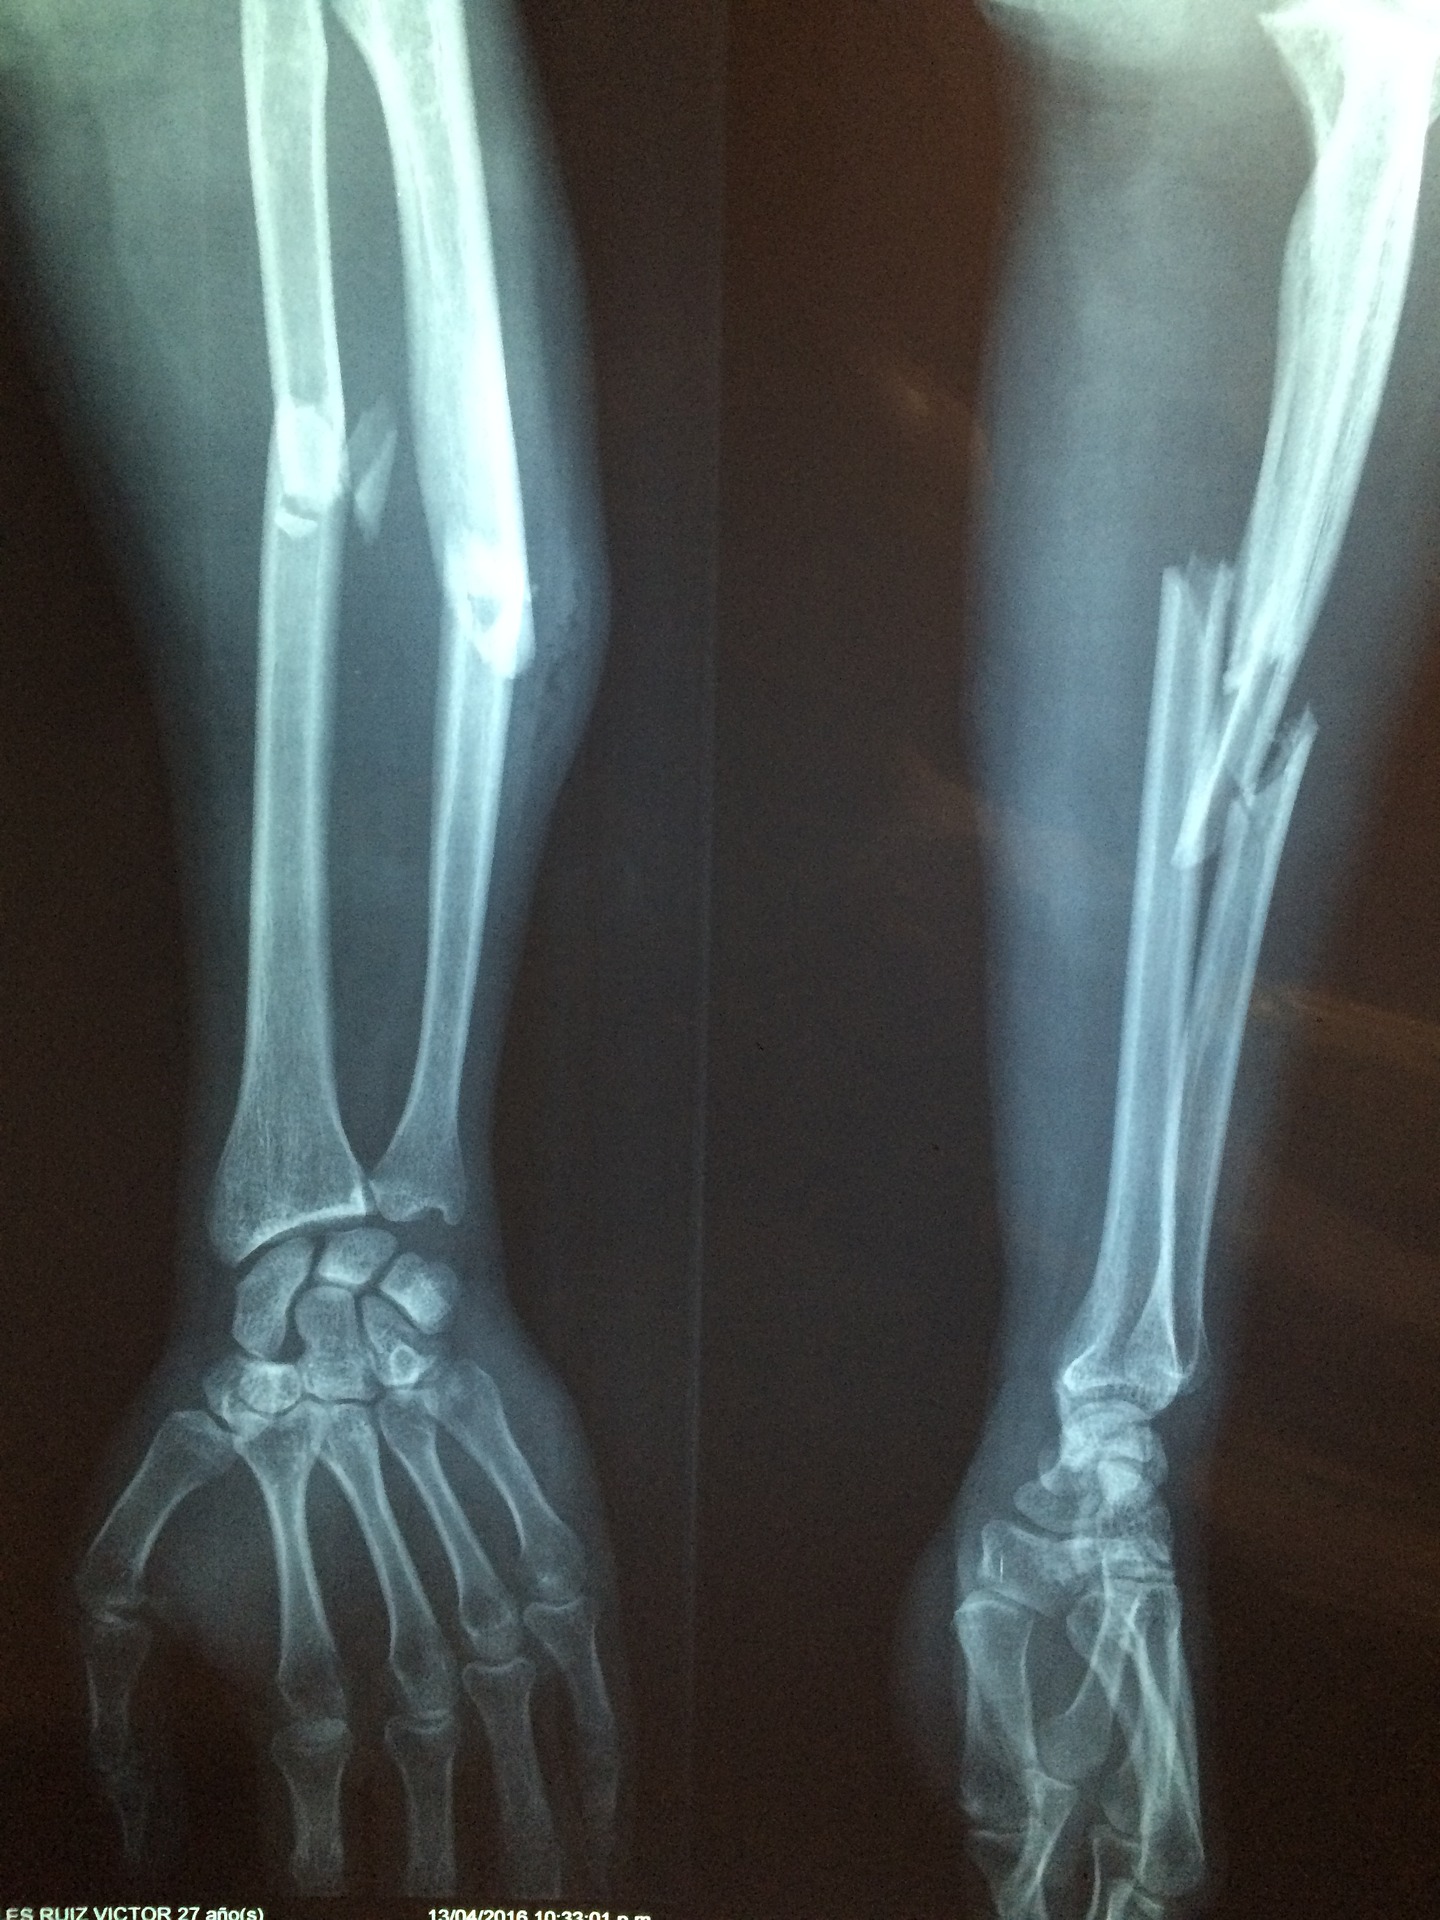

שבר באמה

ניתן לאבחן ע"י קולן לא צריך צילום